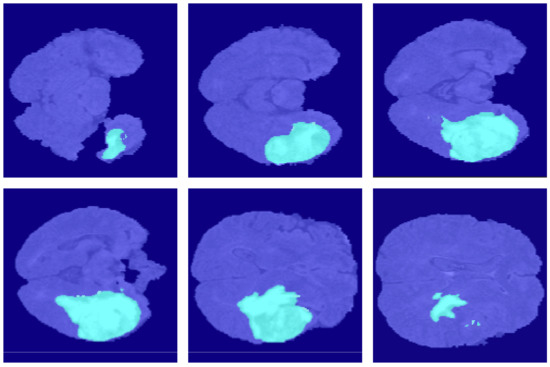

4.2. Segmentation Results

5.6.2. Third Dimensional Information Loss